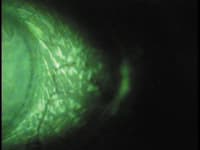

| Pictured are examples of severe bulbar conjunctival staining that can sometimes accompany contact lens dryness. | |